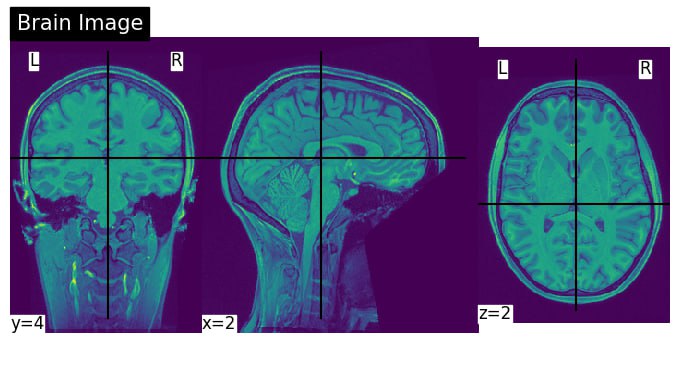

For this poject, we have access to the Brain activities, and its parcellation. Then the main task is decode the Brain activites into different classes. Normally as the data per voxcel in the Brain is a Fmri signal, as a preprocesing stage, this data is represented by different techniqes. Here for this project, beta scores as a linear model fitted to the fmri data has the role to represent this data. Therefor after casting the data to the a space called, beta-space, the data has more meaningful representaiton, and also the connectome as the underlying graph connection of the Brain regions is feeded to the Grpah neural netwrok for message passign between different links of the nodes. Eventually, after the trainig, the netwrok is trying to do a classification task based on the training data. Here is the over all procedure for this project: